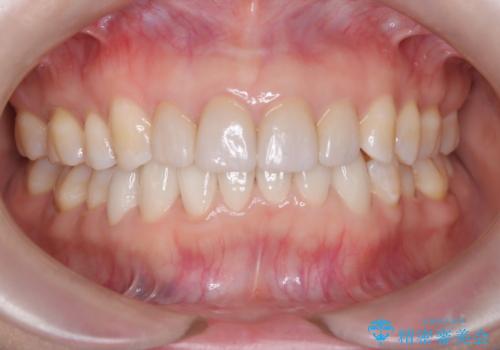

【オールセラミック】下の前歯が痛い。

- 以前に治療した前歯が痛むことを主訴に来院されました。

根っこに病気があり、根管治療から被せ物まで治療を行いました。

根管治療を行った後、3ヶ月間治癒の確認をしてからオールセラミックスペシャルで治療を行いました。